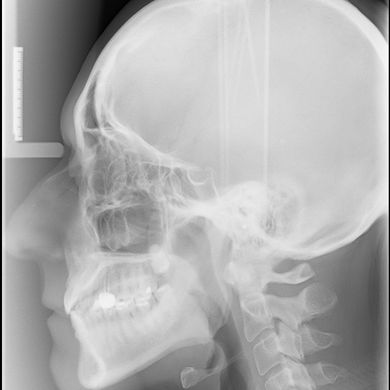

TELERADIOGRAFIA

La teleradiologia cranial es fonamenta en realitzar una radiografia de la cara del pacient. Es du a terme a una major distancia de l’habitual, a uns 2 metres de la placa, de manera que la imatge queda nítida i no es veu distorsionada per les estructures òssies del crani. Ens permet veure amb precisió els ossos de la cara i les dents del pacient. Poden ser frontals o laterals i, a part de ser fonamentals en l’ortodòncia, són molt útils en diagnòstics de patologies com la sinusitis.